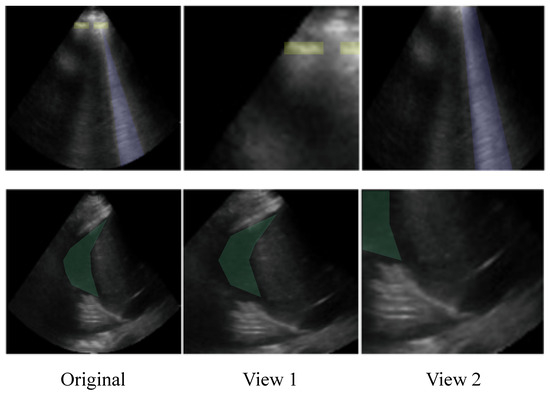

4.7. Impact of the Cropping in Object Classification Tasks

The leave-one-out analysis for transformations exhibited the striking finding that crop and resize (C&R) was the most effective transformation in the StandardAug pipeline for the two object classification tasks: AB and PE. Moreover, both pipelines containing C&R resulted in the greatest downstream test performance on AB and PE. Ordinarily, crops are taken at random locations in an image, with areas between 8 % and 100 % of the original image’s area. Aggressive crops can create situations in which positive pairs do not contain the same objects of interest. Figure 7 shows how C&R could produce positive pairs with different semantic content. Despite this, the results indicated that pipelines containing C&R led to improved performance for the object-centric AB and PE tasks. The exceptional influence of C&R warranted further investigation into its hyperparameters.

Figure 7. Examples of how the random crop and resize transformation (A00) can reduce semantic information. Original images are on the left, and two random crops of the image are on the right. Top: The original image contains a B-line (purple), which is visible in View 2 but not in View 1. The original image also contains instances of the pleural line (yellow) which are visible in View 1 but not in View 2. Bottom: The original image contains a pleural effusion (green), which is visible in View 1 but largely obscured in View 2.